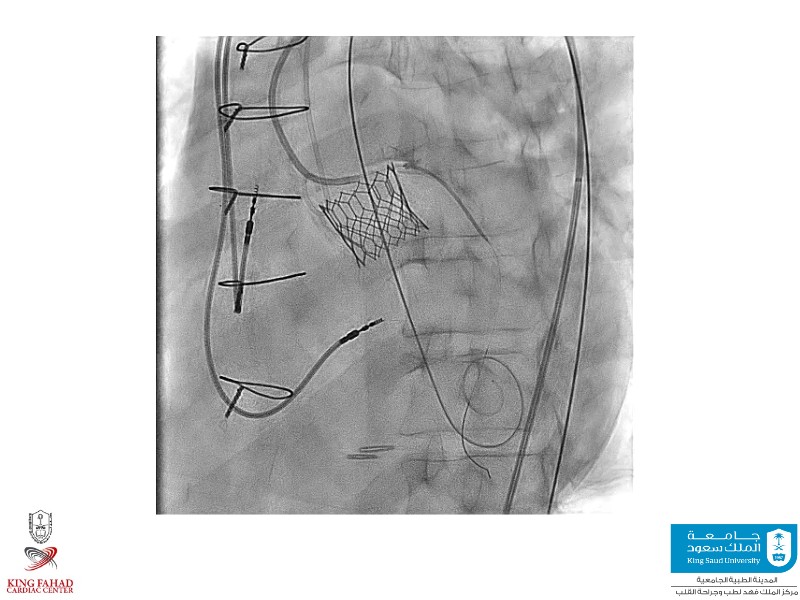

This session helps you anticipate and address complex scenarios such as mitral valve-in-valve, TAV-in-SAV, and valve-in-valve-in-valve procedures. Learn from expert case discussions that explore procedural strategies, technical challenges, and best practices to optimize outcomes in redo structural heart interventions.